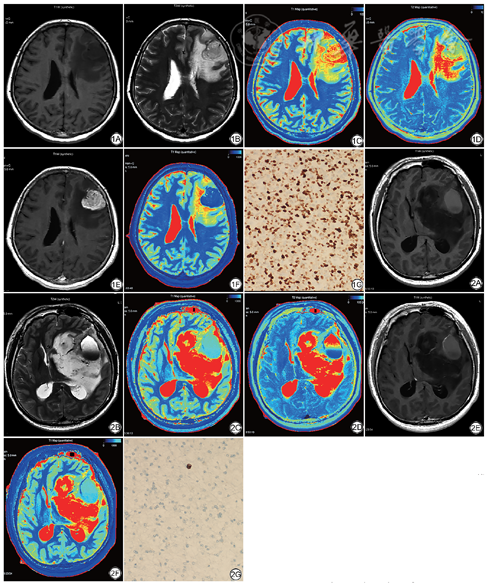

高级别组胶质瘤T1-pre (P=0.006)、ΔT1 (P=0.001)、T1值变化百分比(P=0.003)、Ki-67 LI (P=0.000)明显高于低级别组,T1-Gd (P=0.006)、rT1-Gd (P=0.007)低于低级别组,差异均具有统计学意义。rT1-pre、T2-pre、rT2-pre在两组之间无明显差异(表1)。ROC曲线分析可得T1-pre、T1-Gd、rT1-Gd、ΔT1、T1值变化百分比曲线下面积分别为0.759、0.752、0.746、0.816、0.790 (表2),其中ΔT1对区分高、低级别胶质瘤的效能最好,其最佳诊断阈值为373.25 ms,敏感度为90.5%,特异度为60%,P=0.001。高、低级别胶质瘤的常规MRI、T1 mapping、T2 mapping及免疫组化病理切片如图1、2所示。

T1弛豫时间是MRI的一个基本的物理量,主要受间质含水量的影响[16]。本研究发现,高级别胶质瘤的T1-pre、ΔT1、T1值变化百分比高于低级别胶质瘤,T1-Gd、rT1-Gd低于低级别胶质瘤。这与王佳男等[17]的研究结果基本一致,他们发现增强后T1值及增强后T1值变化的百分比可以区分HGG与LGG,但他们发现增强前T1值在区分高低级别胶质瘤时无统计学意义,这可能是与病例样本量较少有关。经ROC曲线分析得到ΔT1对区分HGG、LGG的效能最高,当ΔT1≥373.25 ms时,倾向于高级别胶质瘤的诊断。因此ΔT1可以作为胶质瘤分级诊断的最佳指标。